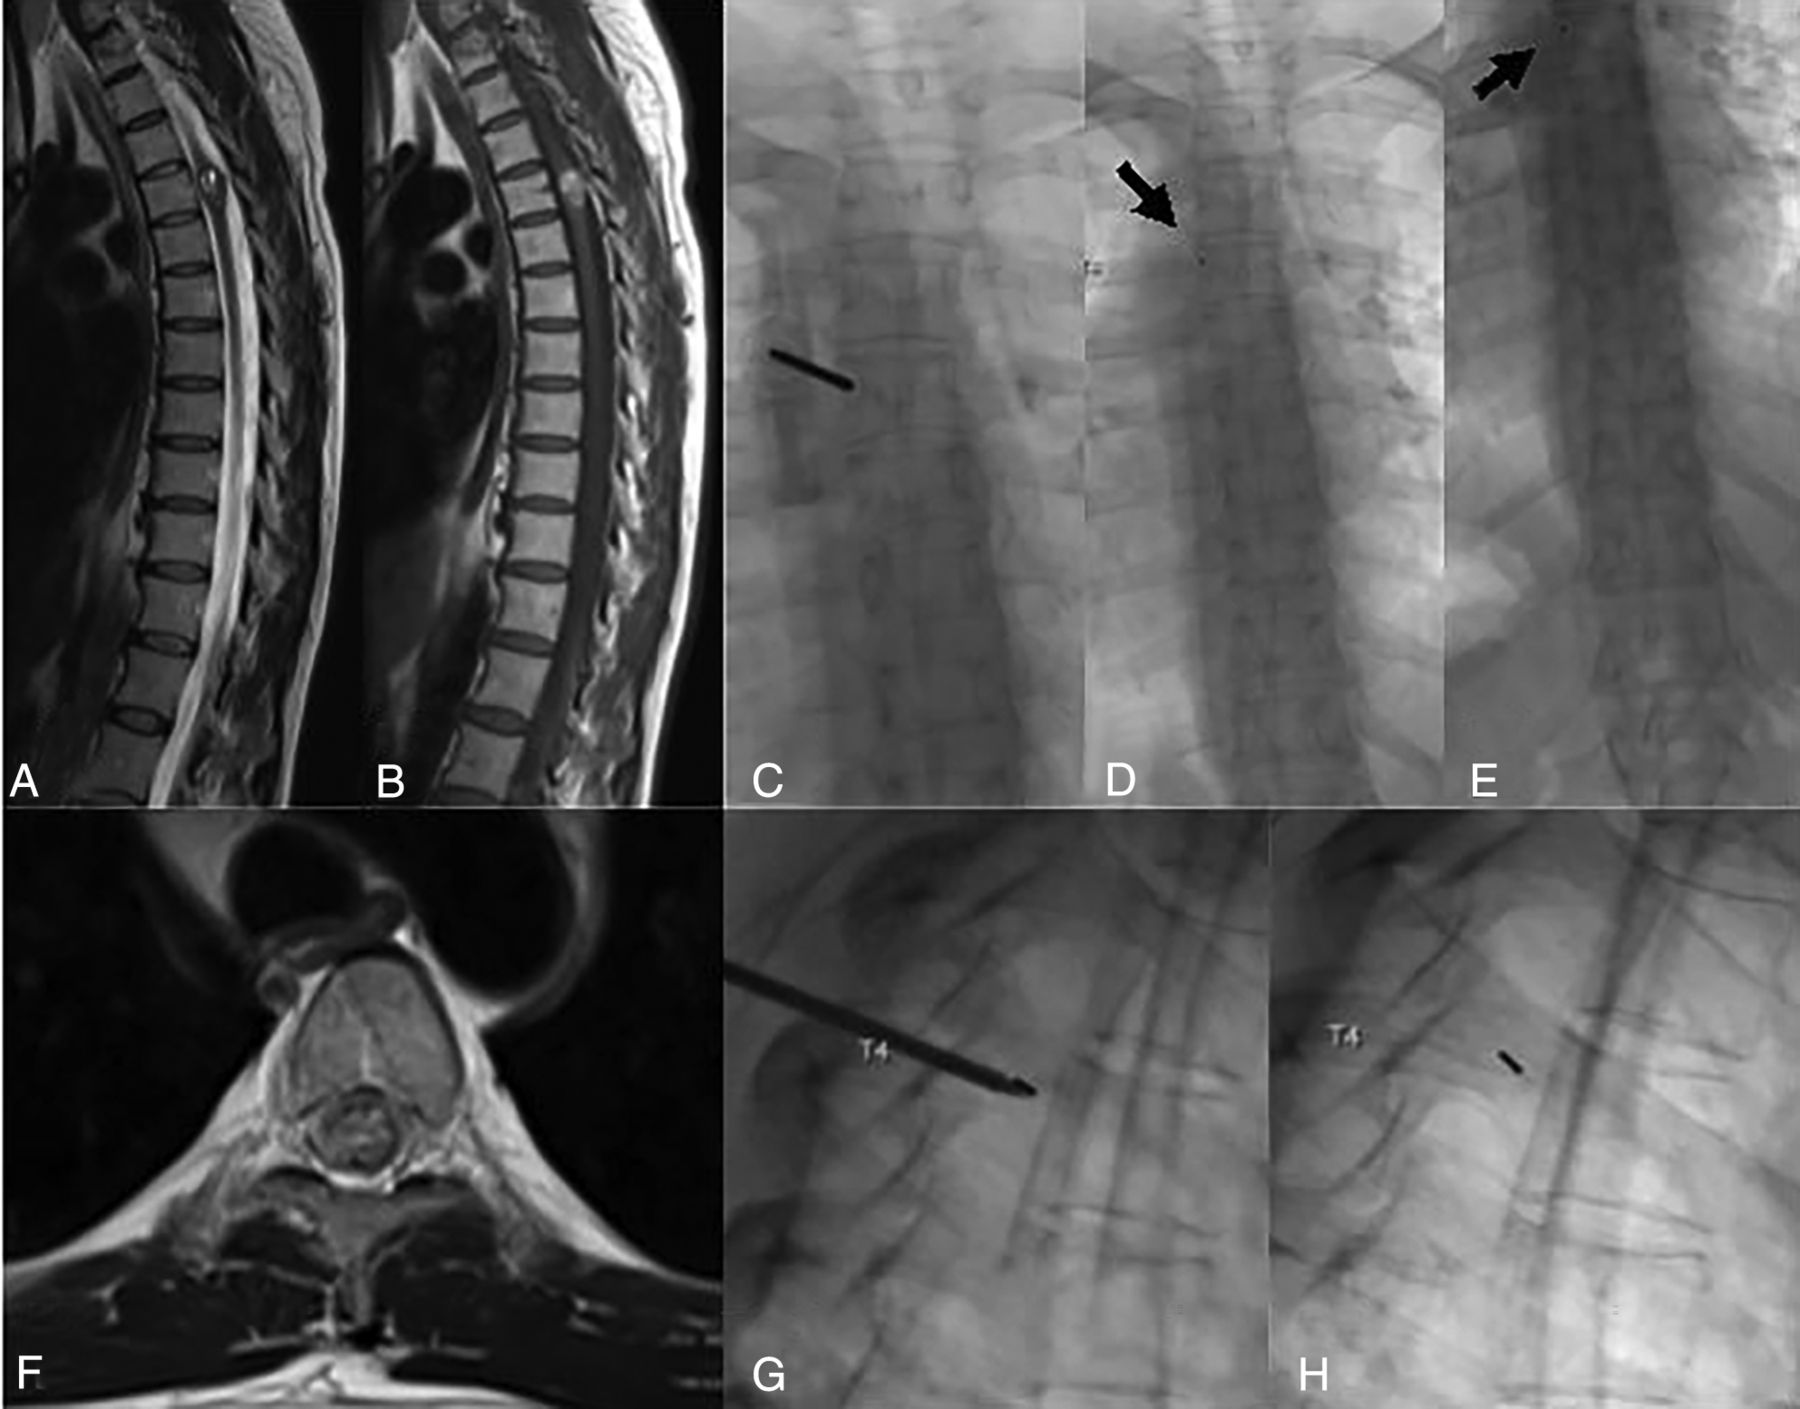

Biplane FL was used to place a gold fiducial marker at T4. Sagittal T2WI (A), sagittal T1WI pregadolinium (B), and axial T2WI (F) demonstrate a multilobulated T1-hyperintense, intramedullary mass with fluid-fluid levels and peripheral T2 hypointensity, which was resected and pathologically proved to be a cavernous malformation. C, Anterior-posterior FL image demonstrates the bone access needle traversing the left pedicle of T4. D and E, Postprocedural images for counting purposes show the first and last ribs, respectively, with the fiducial marker in place (arrow). G, Intraprocedural image demonstrates the coaxial bone access needle with the stylet in place and the gold fiducial at the tip of the needle. H, Subsequently, the needle has been removed, and the gold fiducial remains in place at the junction of the pedicle and vertebral body.